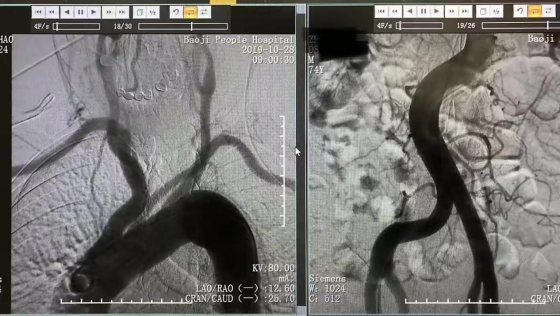

神经内科主任周文斌、主治医师丁源、医师刘鑫查房后,立即为患者完善头部核磁,根据患者症状、体征以及辅助检查,明确诊断为急性脑梗死,颅内血管MRA提示双侧椎动脉及基底动脉节段性狭窄,有行脑血管造影指征,需进一步评估患者颅内血管情况。主任医师张先龙为李先生和妻子介绍可以开展新技术,经桡动脉行脑血管造影检查,术后可以从介入手术室走回病房,无需卧床休息且舒适度高,恢复快,可以避免长时间卧床引起的不适和痛苦,如:腰痛,尿潴留等,同时也避免了卧床期间大小便需要他人护理的尴尬。

随着影像技术的发展,越来越多的无创技术如CTA、MRA等用于临床评估脑血管的情况,但选择性脑血管造影作为一种有创的脑血管检查,仍是目前评估脑血管的“金标准”,经股动脉入路全脑血管造影术已经成为常规方法,就桡动脉来说血管变异及迂曲多,在手术技术方面仍存在一些难度,但对患者术后护理更方便,舒适度更高。患者及家属对医护人员表示由衷感谢。

主任医师张先龙表示:经桡动脉全脑DSA较经股动脉具有诸多优点,一是对穿刺局部损伤小,出血少,术中及术后并发症少且轻微,术后护理方便安全,二是术后即可下床活动,舒适度好,患者易于接受,尤其对于老年人,三是术后不需长时间制动,四是对于股动脉狭窄/闭塞或既往曾发生过股动脉严重并发症的患者,可以作为另一备用选择。由于该术式的诸多优点,大大地提高了患者接受脑血管造影这一血管检查金标准的程度。 编辑:胡泽涛 编审:李 晓 终审:胡卫锋